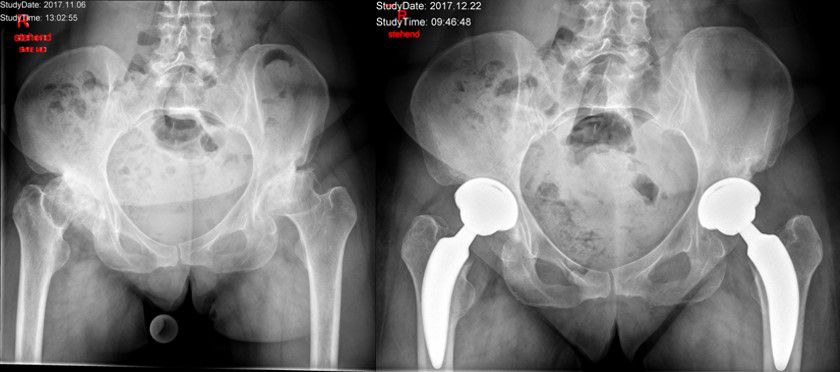

Bei operationspflichtiger Abnützung des Hüftgelenkes wird die Implantation eines künstlichen Hüftgelenkersatzes durchgeführt. Die dabei verwendete OP-Technik ist minimal invasiv, d.h. dass durch die Operation keine Muskeln durchtrennt werden. Die einzelnen Muskeln werden während der Operation wie Jalousielamellen auseinandergehalten. Dadurch wird eine rasche Mobilisierung nach der Operation möglich. Im Idealfall können Sie bereits am ersten Tag nach der Operation mit physiotherapeutischer Hilfe unter Vollbelastung gehen. Die Verankerung der Prothesenteile erfolgt in den meisten Fällen zementfrei.

Die am häufigsten eingesetzte Gleitpaarung ist Keramik-Keramik. Bei passender Form und Knochenqualität des Oberschenkelknochens besteht die Möglichkeit, einen Kurzschaft zu implantieren. Die unmittelbaren Vorteile eines Kurzschaftsystemes liegen in einer noch knochensparenderen und muskelschonenderen Implantationsmöglichkeit sowie einer physiologischen Krafteinleitung in den Knochen. Ob diese Vorteile auch im Langzeitverlauf gelten, ist derzeit Gegenstand wissenschaftlicher Forschung. Die kurz- und mittelfristigen Ergebnisse sind aber durchaus vergleichbar mit Standardschäften.